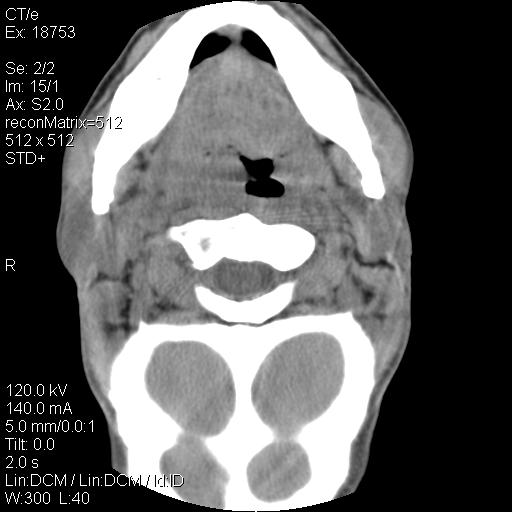

标题: CT21693:男 58岁 右侧咽部疼她2天余 PE:右侧扁桃体肿大 压痛 [打印本页]

标题: CT21693:男 58岁 右侧咽部疼她2天余 PE:右侧扁桃体肿大 压痛

右化脓性扁桃体炎症伴咽后壁脓肿形成.

结合病史,考虑感染性病变;建议抗炎治疗复查排除肿瘤性病变。

弥漫性肿胀,与周围组织分界不清,发病急,有明显症状,考虑:感染性病变! 抗炎后复查。